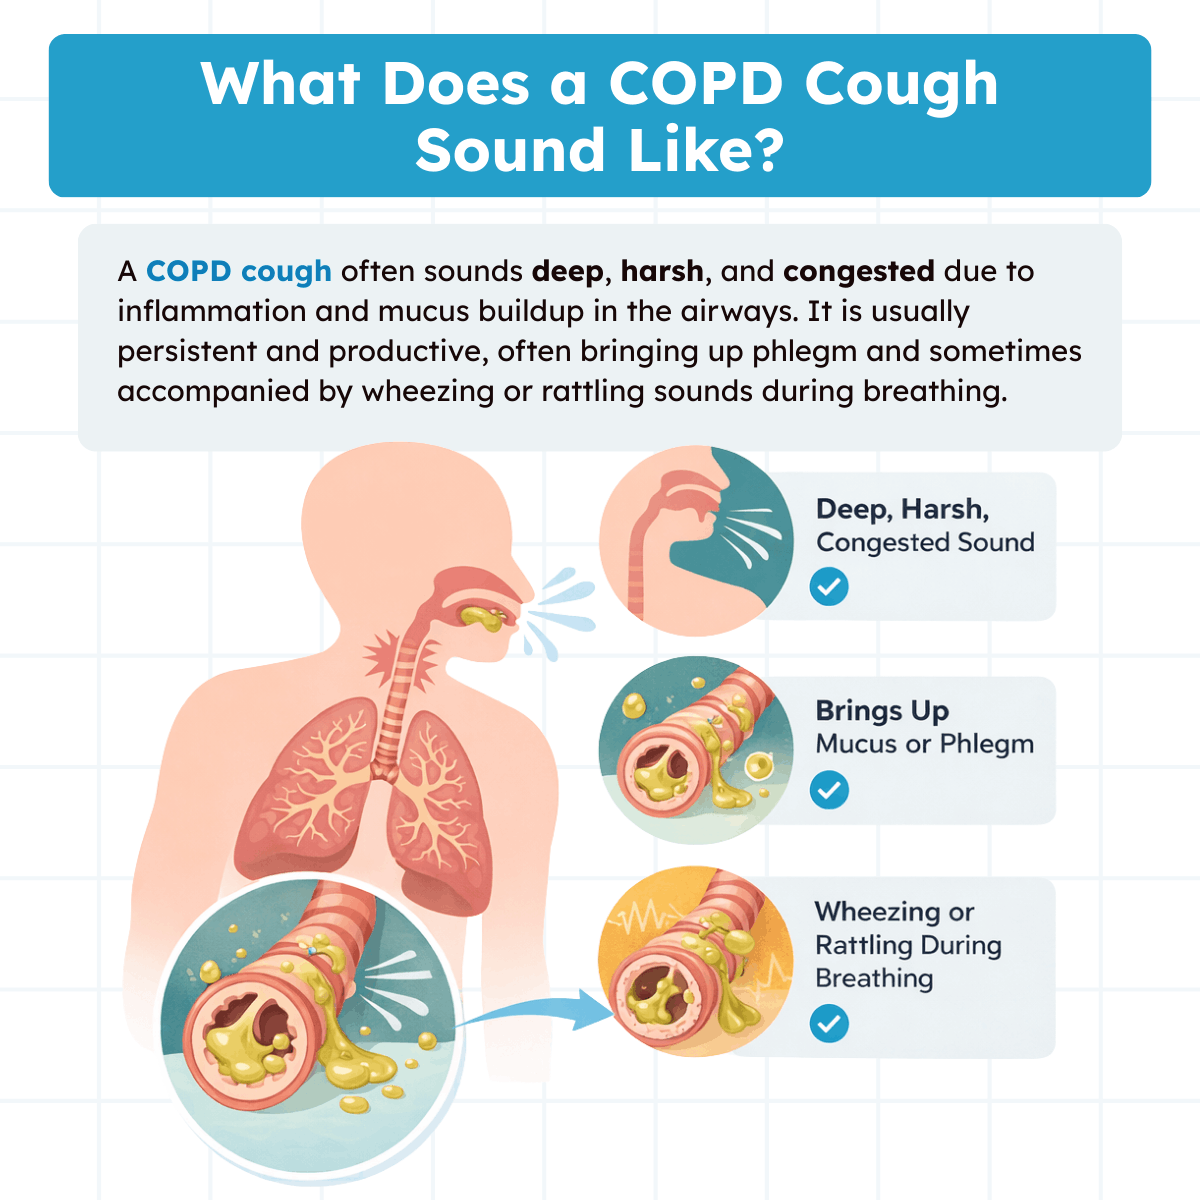

What Does a COPD Cough Sound Like?

A COPD cough is typically deep, persistent, and often described as “wet” or productive. Unlike a dry cough, it frequently brings up mucus or phlegm from the airways, especially in the morning. The sound may be harsh, rattling, or congested due to inflammation and excess mucus in the bronchial tubes.

Many people with COPD experience repeated coughing fits as the body tries to clear secretions from narrowed airways. In some cases, the cough may also be accompanied by wheezing, chest tightness, or shortness of breath.

Because COPD causes long-term airway irritation, this cough tends to occur daily and may worsen during respiratory infections, exposure to smoke, or other environmental irritants.